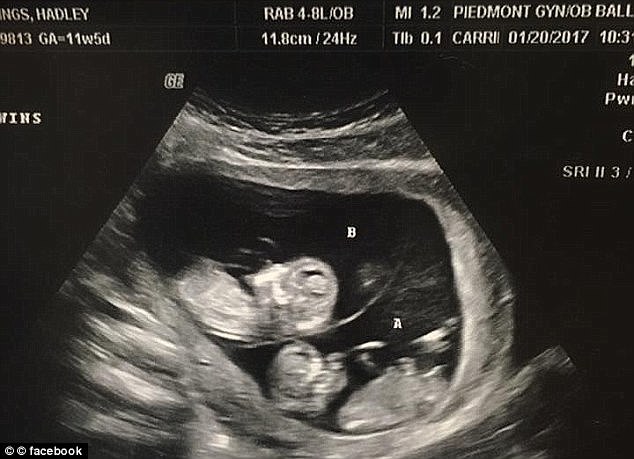

▼兩年之後,哈德莉再度懷孕而且還是雙胞胎,他們相信是上帝補償給他們的孩子,於是將會用死去的兩個兒子名字來為他們命名。

▼在今年的7月10日,這對雙胞胎終於誕生了!